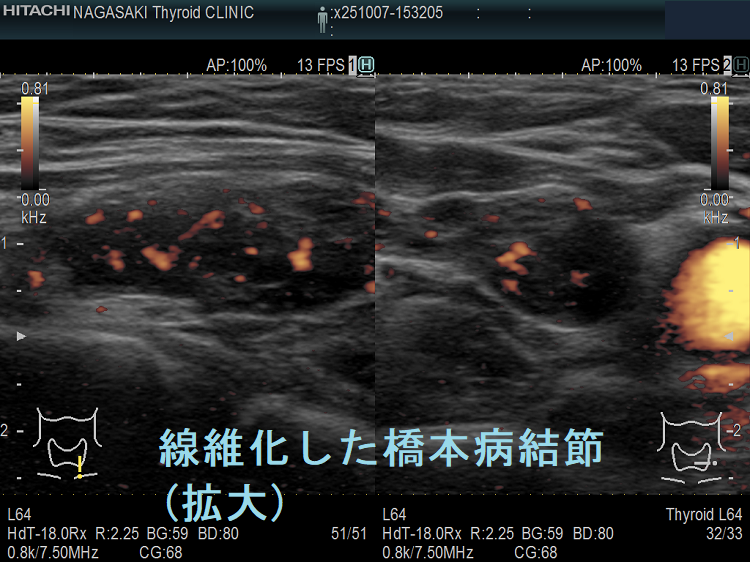

橋本病(慢性甲状腺炎)ではリンパ球浸潤に伴う炎症から濾胞細胞の好酸性変性[好酸性細胞(Hürthle細胞,ハーテル細胞)]・過形成、浮腫、線維化で結節性病変を形成[結節性橋本病(橋本病結節)]。病理学的に腺腫様甲状腺腫・腺腫様結節と同じで、橋本病(慢性甲状腺炎)を基盤とする腺腫様甲状腺腫・腺腫様結節。超音波(エコー)検査では内部が極めて低エコーのため甲状腺癌、甲状腺原発悪性リンパ腫と鑑別必要。細胞診では好酸性細胞、リンパ球集簇、炎症性多核巨細胞を認め、甲状腺乳頭癌ワルチン腫瘍型、通常型甲状腺乳頭癌・亜急性甲状腺炎と鑑別要。

橋本病(慢性甲状腺炎)では、リンパ球浸潤に伴う炎症から、濾胞細胞の好酸性変性・過形成、浮腫、線維化などの変化で結節性病変が形成されます[結節性橋本病(橋本病結節)]。病理学的には腺腫様甲状腺腫・腺腫様結節と同じ事で、橋本病(慢性甲状腺炎)を基盤とする腺腫様甲状腺腫・腺腫様結節になります。

橋本病リンパ球浸潤、橋本病結節 どちらともとれる見え方です。境界がはっきりしているので橋本病結節とも言えるし、炎症性変化が主体なので橋本病リンパ球浸潤とも言えます。